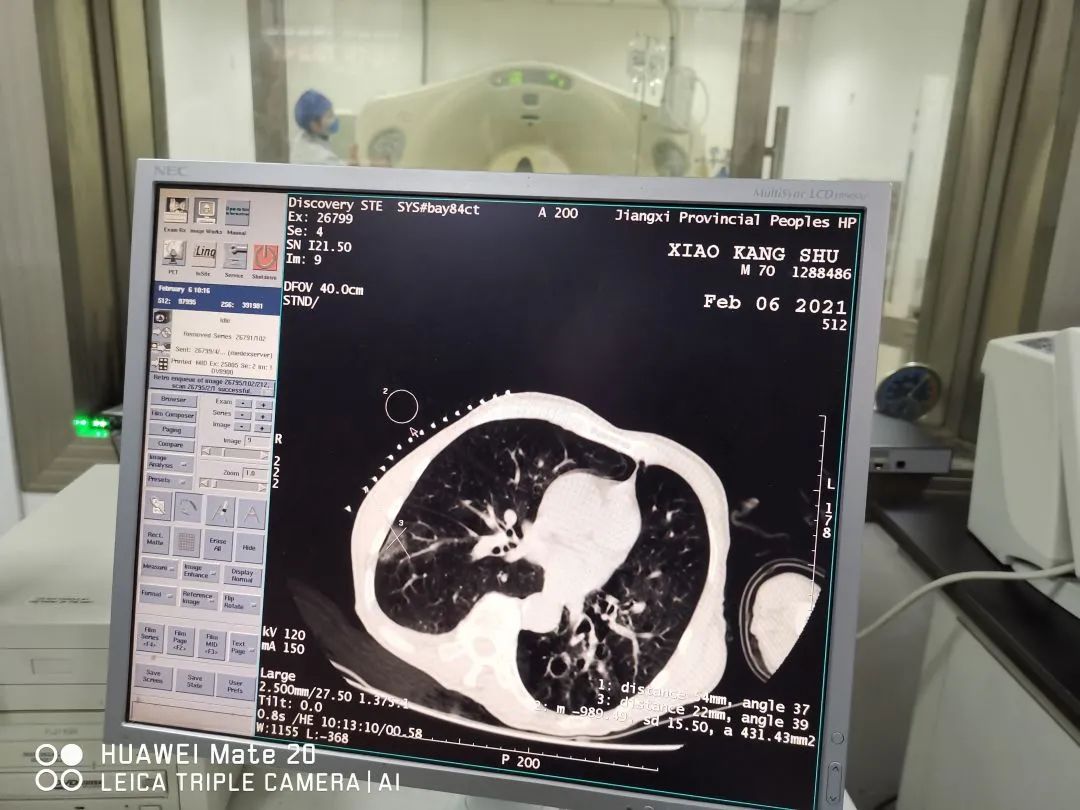

患者70岁男性,右肺下叶磨玻璃结节,穿刺病理原位腺癌

消融治疗后病灶呈“荷包蛋”样改变,肿瘤彻底清除